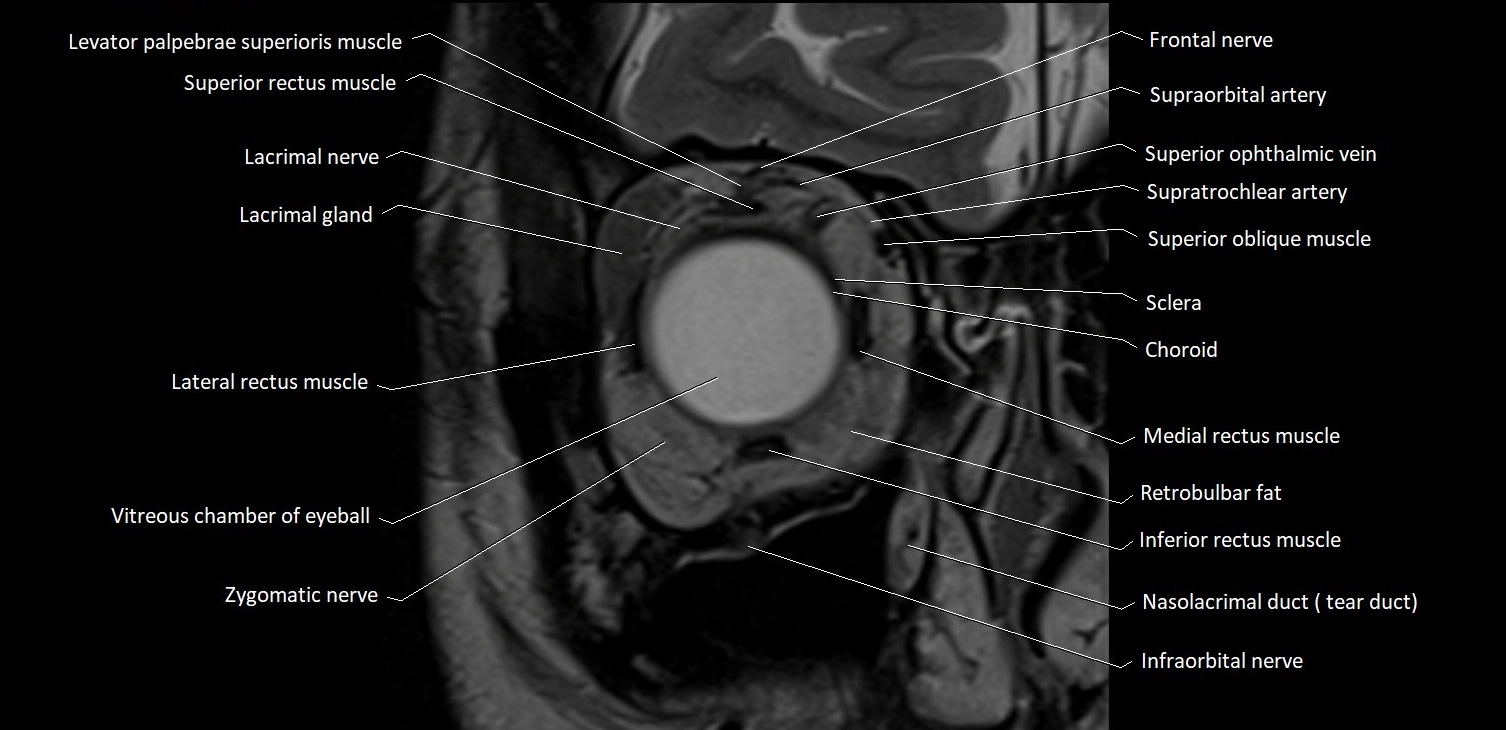

MRI images